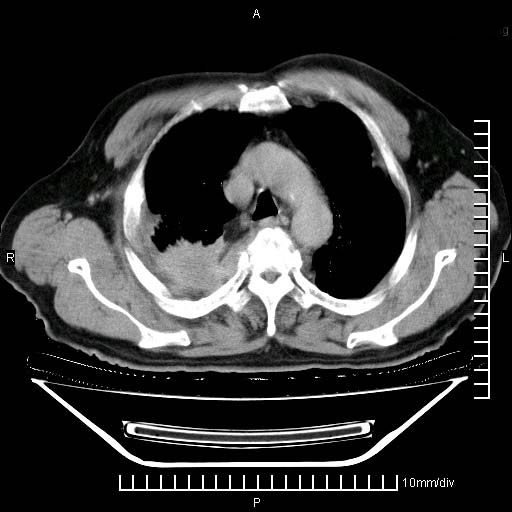

标题: CT24043:胸部增强:男性,60岁

既往肺结核,近10几天,咳嗽,咳痰,右侧胸痛,疼痛较明显,右上肺斑块考虑结核灶胸膜粘连,增强,可惜动脉期没有定好,未见强化,可延迟4分后又见较明显强化,中心见低密度影,如果说结核是边缘强化,可这个灶强化的面积挺大的,让人很挠头。

延迟4分后